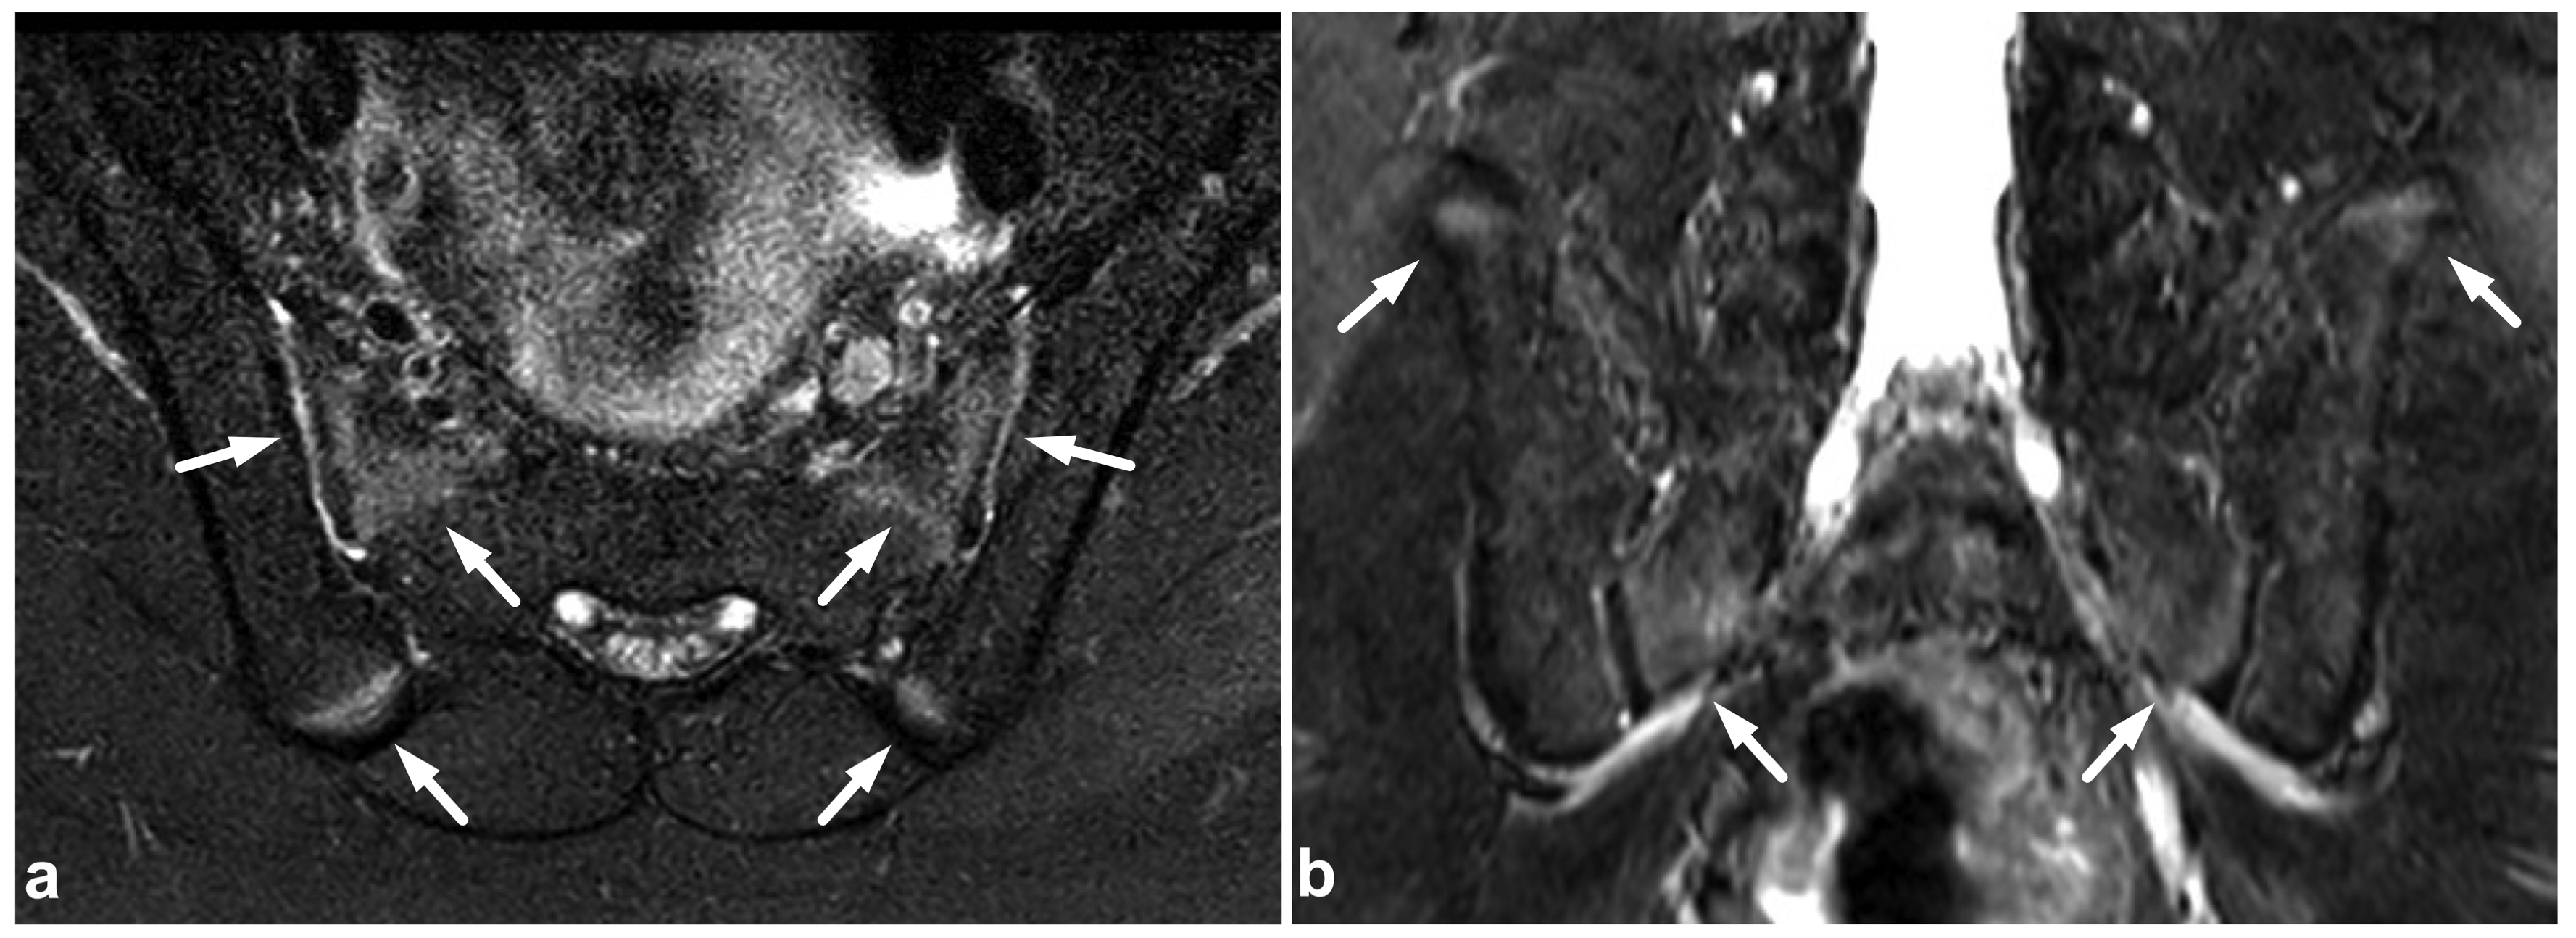

7.4. Imaging Appearances of Normal Skeletal Maturation

Every radiologist performing pediatric imaging must be aware of the fundamentals of skeletal maturation [87]. On the MR imaging of acute pediatric trauma, one of the potential pitfalls is the physiological high T2 signal at the physis and metaphyseal spongiosa of the secondary ossification centers [88]. This can be misinterpreted as traumatic edema if the normal anatomy and development of the ossification centers are not kept in mind (Figure 20). On the other hand, an unfused vertebral ring apophysis [89,90], apophyseal injuries [91], and other calcifications not related to the acute injury are readily distinguished from fractures with the absence of edema (Figure 21).

Figure 20.

(a) Axial fat-suppressed T2-weighted. (b) Coronal STIR. An 11-year-old male, lower back/pelvic pain after falling on ice. MRI demonstrates symmetric zones of bright T2 signal (arrows) at the secondary ossification centers of the sacrum and iliac bone, characteristic of normal skeletal maturation. With the symptoms and injury mechanism in such a case, the findings could be misinterpreted as traumatic edema if the normal skeletal maturation and anatomy of the ossification centers are not kept in mind.